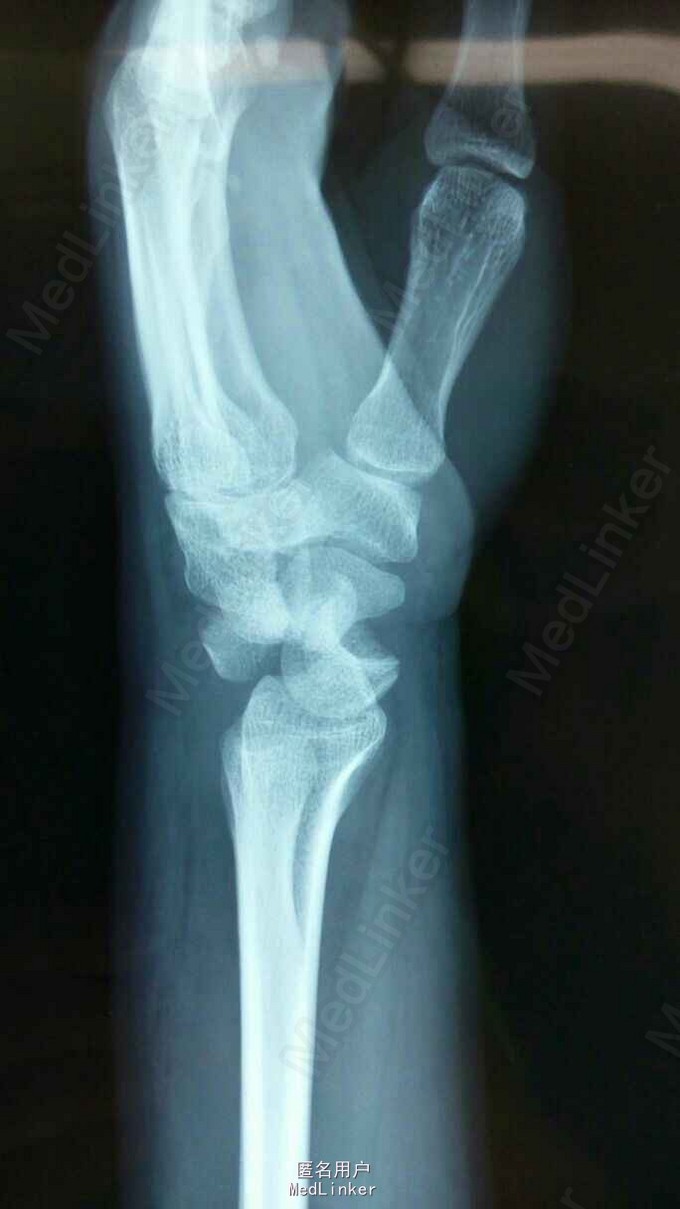

经舟骨月骨周围脱位

患者1天前骑摩托车摔伤致左腕部肿痛不适,活动受限,桡侧三个半手指麻木不适

腕关节肿胀明显,桡侧三个半手指感觉迟钝,腕关节住被动活动受限

经舟骨月骨周围脱位,闭合复位失败后,行手术治疗,月骨切开复位,舟骨空心钉固定